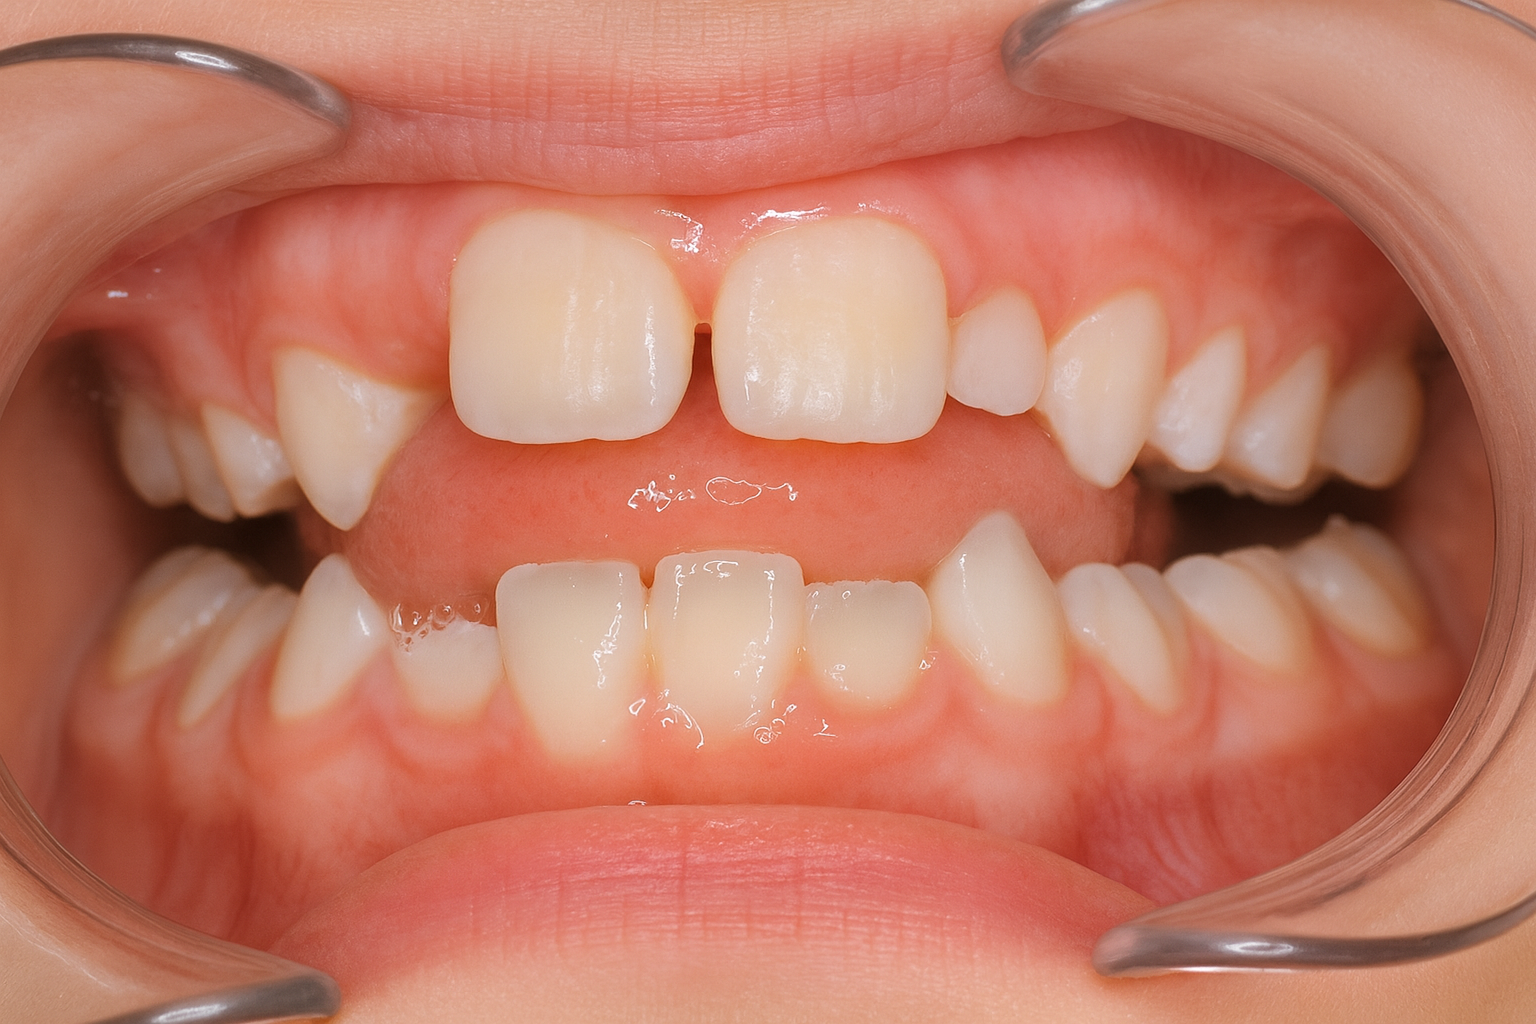

↑ 隙間が自然と埋まることも多いとされています

「いわゆる“醜いアヒルの子”期(Ugly Duckling stage)」とは、大人の歯と子供の歯が混ざった小学生の時期、医学的には混合歯列期において、上あごの中央付近、左右の永久中切歯が外側に傾斜することで、中央に隙間(正中離開/diastema)が生じる現象を指します。

文献的には、この隙間(正中離開)は混合歯列期に比較的高頻度にみられ、上顎の側切歯・犬歯が萌出を進める段階で自然に閉じていくことが多い、という報告が古くからあります。

そのため、基本的な方針としては「この時期(混合歯列期)では、まず経過観察でも良い場合が多い」というスタンスをとることが一般的です。